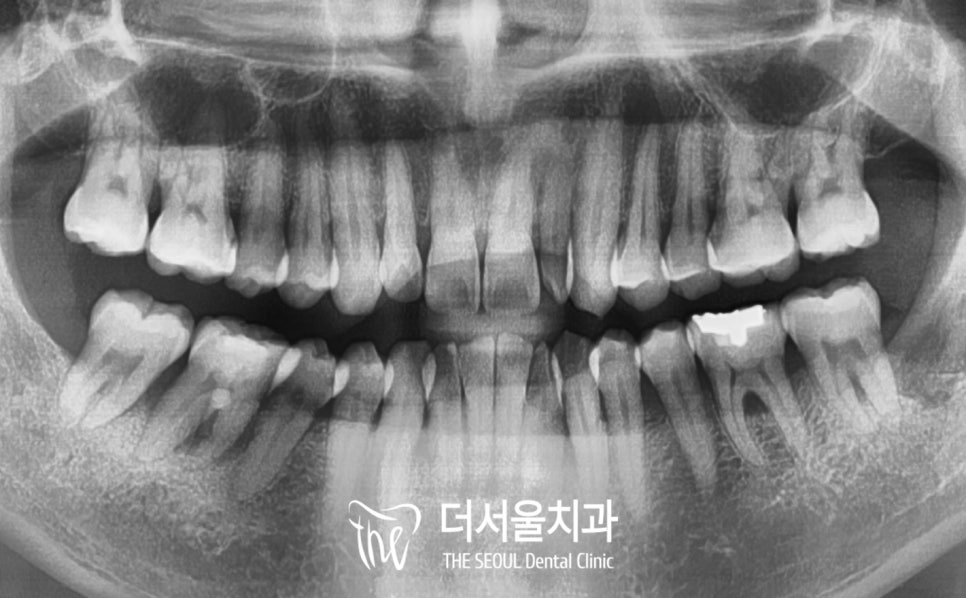

이를 뽑은 다음 촬영한 X-Ray 인데요.

깔끔하게 잘 비워졌죠?

며칠이 지나지 않아

봉합해놓은 실밥을 제거하러 오셨을때,

환자분 역시 깔끔하게 잘 비워져

마음이 편해졌다고 그렇게 말씀해주셨습니다.